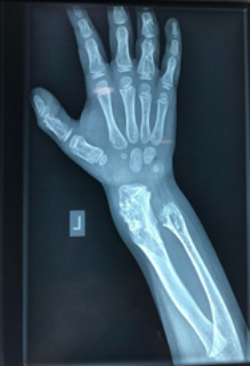

Olier’s disease

The images show a case of Olier’s disease which had a short and deformed forearm. He underwent surgical intervention by Dr. Zenios with the use of external osteosynthesis.

Pre-operative

External osteosynthesis